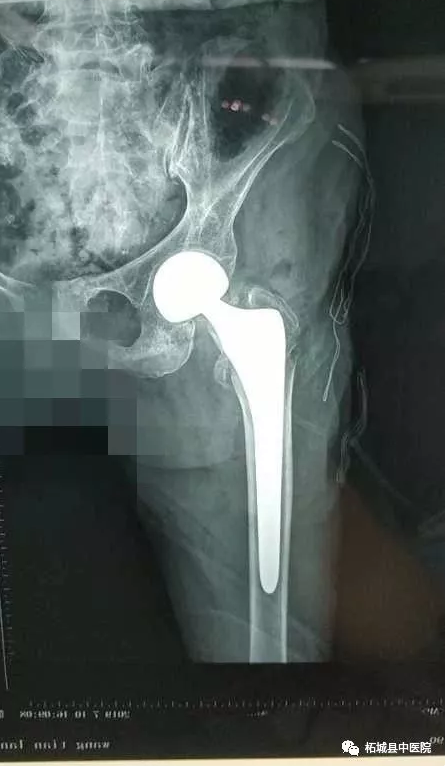

该老人是一位基础疾病较多的患者,详细检查后,老太太骨折合并有贫血、低蛋白血症、慢性阻塞性肺炎,保守治疗需长期卧床,可能导致坠积性肺炎、褥疮、下肢静脉血栓形成、骨折不愈合等并发症威胁患者生命安全,请北关院区呼吸科王因仲主任、胸痛中心孙全立主任会诊评估,经过多番讨论和家属沟通,参考我院曾经做过多例百岁老人关节置换术后第二天下床走路病例, 终确定人工髋关节置换术的治疗方案。

7月10日下午,在中医院北关院区百级层流净化手术室,殷晓东院长带领骨二科医师团队亲自手术,麻醉师张文选全程监控,内科专家王因仲、孙全立随时待命。仅耗时20分钟就顺利地完成了主操作。当老人被平安送出手术室的一刻,柘城中医院乃至柘城县 高龄髋关节置换手术患者的纪录也再次被刷新。